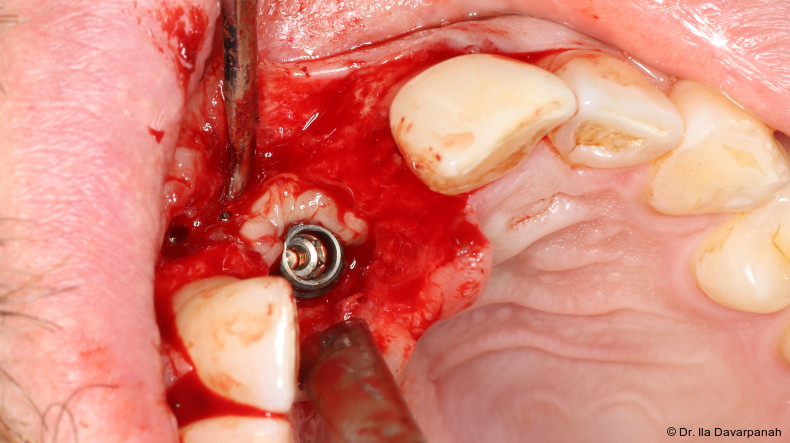

Zur Erreichung einer hohen Primärstabilität wurde ein Implantat mit aggressivem Gewinde bei einem Außendurchmesser von 3,5 mm und einem Kerndurchmesser von ca. 2,8 mm eingesetzt. Ergänzend erfolgte eine unterpräparierte Bohrung. Solche Kombinationen aus Gewindedesign, Implantatgeometrie und Bohrprotokoll sind in der klinischen Praxis etabliert, erfordern jedoch eine sorgfältige Risikoabschätzung hinsichtlich der mechanischen Belastung des Implantatkörpers.

Komplikation: Implantatfraktur

Postoperativ kam es trotz korrekter Implantatpositionierung und regelrechter Sofortversorgung zu einer Fraktur des Implantatkörpers im Bereich der Implantatschulter. Die radiologische Diagnostik mittels Röntgen und DVT zeigte ein Aufplatzen des Implantats im Übergangsbereich zwischen Konusverbindung und Implantatplattform. Das Frakturmuster deutete auf eine strukturelle Überlastung im hoch beanspruchten Schulterbereich hin. Implantatfrakturen stellen insgesamt eine seltene, jedoch für Patient und Behandler belastende Komplikation dar. Sie treten bevorzugt in Regionen mit erhöhten Biege- und Querkräften auf, insbesondere in der Frontzahnregion und bei frühzeitiger funktioneller Belastung.